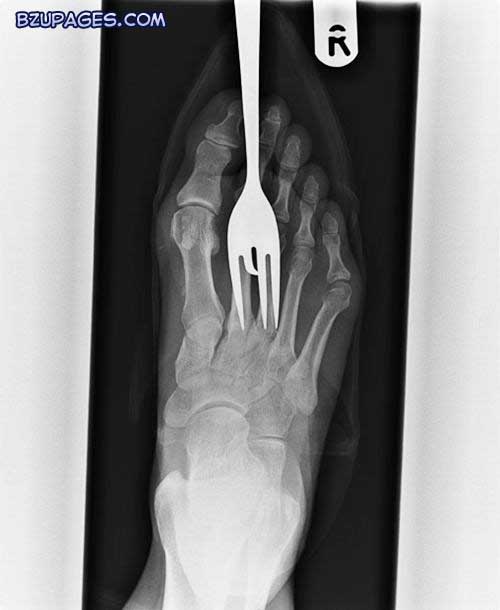

An X-ray of the foot of a patient who stood on a fork

Another patient who stood on a fork